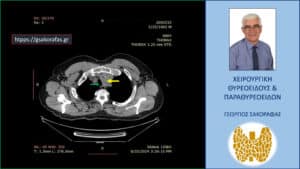

Αξονική τομογραφία – εγκάρσια διατομή στο ύψος περίπου των στερνοκλειδικών αρθρώσεων. Ο καταδυόμενος αριστερός λοβός (κίτρινο βέλος) απωθεί την τραχεία (πράσινο βέλος) προς τα δεξιά.

Αξονική τομογραφία – εγκάρσια διατομή σε χαμηλότερο επίπεδο σε σχέση με την προηγούμενη εικόνα. Ανάλογα ευρήματα.